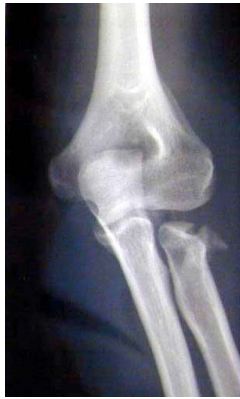

Il est important de différencier la contusion du coude, en particulier la blessure au coude chez l'enfant, des entorses, des dislocations et des fractures L'enfant est très clairement vu limiter les mouvements de flexionextension, le bras souvent blessé, il essaie de maintenir sa main, en plus d'un œdème osseux de coude cassé est. Fracture pilon tibial Fracture bimaléollaire avec luxation Fracture de la cheville Fracture tête radiale coude droit avec prothèse inerte Fracture du lifranc avec fracture déplacée du premier cunéiforme Marcher correctement apres fracture Tibia/Peroné Plus de sujets relatifs à. L’entorse légère Douleur immédiate, qui peut disparaître rapidement mais revenir de manière lancinante au bout de quelques heures Les mouvements sont possibles;.

Un traumatisme isolé du coude doit faire rechercher une lésion associée à l’épaule, au bras, à l’avantbras et au poignet a) ostéoarticulaire b) vasculonerveuse Le coude doit être mobilisé précocement à cause du risque de raideur posttraumatique ou postopératoire 21 Luxation du coude. > au développement d’une l’arthropathie acromioclaviculaire Traitement chirurgical des entorses acromioclaviculaires de stade 4 et 5 Dans les stades 4 et 5 les l’ensemble des attaches ligamentaires sont rompues et entraîne une perte de contact entre acromion et clavicule. • au pli du coude (tendinite du biceps) • à l’arrière du coude (tendinite du triceps) Pour soigner une tendinite du coude, il faut appliquer les remèdes naturels suivants 1) Mettre au repos le coude et le poignet Pour commencer, vous devez arrêter toutes les activités augmentant la douleur.

Examen clinique du coude pour entorse du ligament latéral interne https//wwwsportsanteconseilorg/support/helpus. L'entorse est un étirement ou une déchirure d'un ou de plusieurs ligaments d'une articulation Les principaux symptômes d'une entorse sont la douleur et l'inflammation locale puis un oedème, des spasmes peuvent aussi intervenir Dans tous les cas, c'est le froid qui est recommandé, il ne faut pas mettre de chaleur ni masser Mettez votre articulation et vos muscles alentour au repos et. Conduite à tenir (2) • Si le coude ne se reluxe pas en extension – Stabilité au testing • Attelle en flexion 90° pendant quelques jours puis rééducation – Instabilité au testing • Orthèse articulée maintenant l’avantbras en pronation • Si le coude se reluxe en extension – Immobilisation trois semaines en flexion.

Entorse au coude Avezvous une douleur au coude suite à un accident soit un coup ou une torsion La douleur peut être à l’intérieur, à l’extérieur ou diffuse au niveau du coude. L’entorse du coude est la lésion des ligaments situées entre l’humérus et l’ulna (cubitus) au niveau du coude ou entre le radius et l’ulna (cubitus) Si l’entorse est importante, cela peut aboutir à la luxation du coude Comment apparaît une entorse du ligament collatéral médial du coude?. Les tendinites au coude ne touchent pas que les sportifs mais peuvent également survenir chez les personnes effectuant des mouvements répétitifs (menuisiers, maçons, jardiniers, etc) En effet, une sollicitation excessive des tendons entraîne des microt.